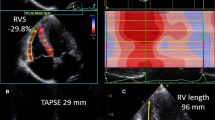

Semi-quantitative RV parameters (TAPSE, RVFS and RVFAC) were determined using a 4-chamber view cine sequence (Fig. 1). TAPSE is the difference between ED and ES RV length. These lengths are measured from the lateral part of the tricuspid annulus to the RV apex. RVFS is the TAPSE indexed to the ED RV length. To determine RVFAC, ED and ES RV areas were measured on a 4-chamber view; RVFAC was obtained by dividing the difference between the ED and ES areas by the ED area. As for Qt measurements, trabeculae and papillary muscles were included in the RV cavity for RVFAC measurement. For all SQt measurements, RV ED and ES were defined respectively as images with the largest and the smallest RV cavity area. To evaluate intra- and inter-observer variability and the effect of previous experience, each SQt analysis was performed twice at least 1 month apart.

Reproducibility of semi-quantitative parameters

All observers had lower intra-observer variability for RVFAC compared with RVFS and TAPSE (Fig. 2, Table 3). Intra-observer variability of RVFAC was less subject to initial observer experience (CV and ICC ranging respectively from 6.7% and 0.955 for Obs1 to 13.8% and 0.825 for Obs3). Intra-observer variability was more experience-dependent for both RVFS (CV and ICC ranging respectively from 11.3% and 0.906 for Obs1 to 23.8% and 0.760 for Obs3) and TAPSE (CV and ICC ranging respectively from 11.6% and 0.912 for Obs1 to 26.0% and 0.756 for Obs3).

Inter-observer reproducibility (Fig. 3, Table 4) was good for RVFAC (CV and ICC ranging respectively from 7.7 to 10.5% and 0.825 to 0.937) and better than for RVFS (CV and ICC ranging respectively from 19.3 to 25.2% and 0.675 to 0.774) and TAPSE (CV and ICC ranging respectively from 21.0 to 25.3% and 0.709 to 0.784).